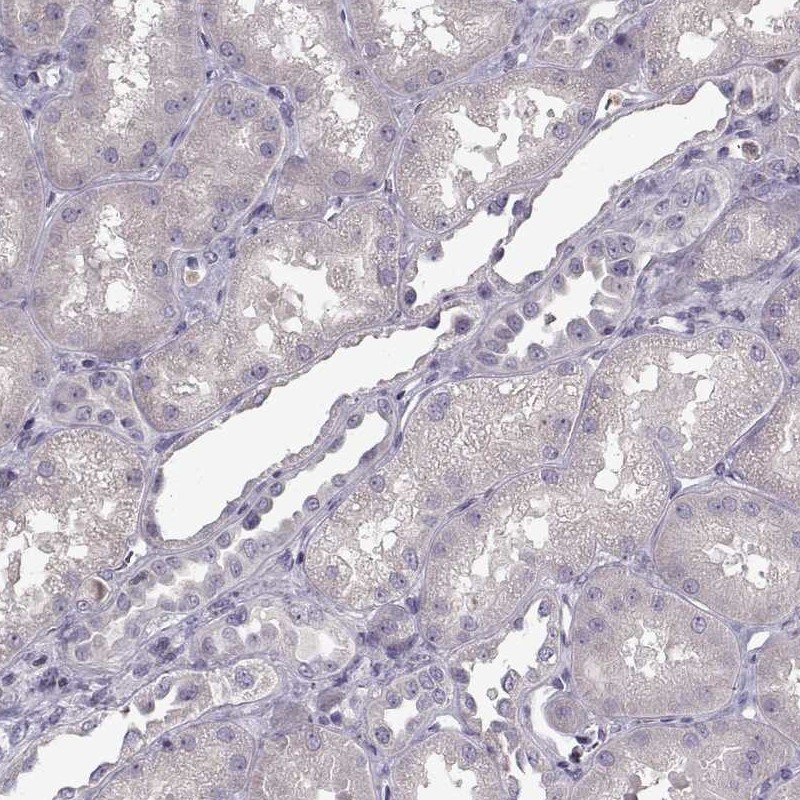

Immunohistochemistry analysis in human spleen and kidney tissues using Anti-UNC13D antibody. Corresponding UNC13D RNA-seq data are presented for the same tissues.